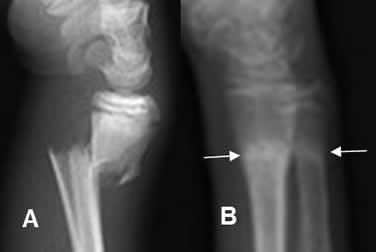

Fig 80 B. Reparación.

A: Rx lateral. Fracturas desplazadas del radio y cúbito distal, con angulación posterior de los fragmentos.

B: Rx lateral. Proyección 2 meses después. Osteoporosis por desuso. Adecuada reducción y alineación, con formación de callos óseos densos.